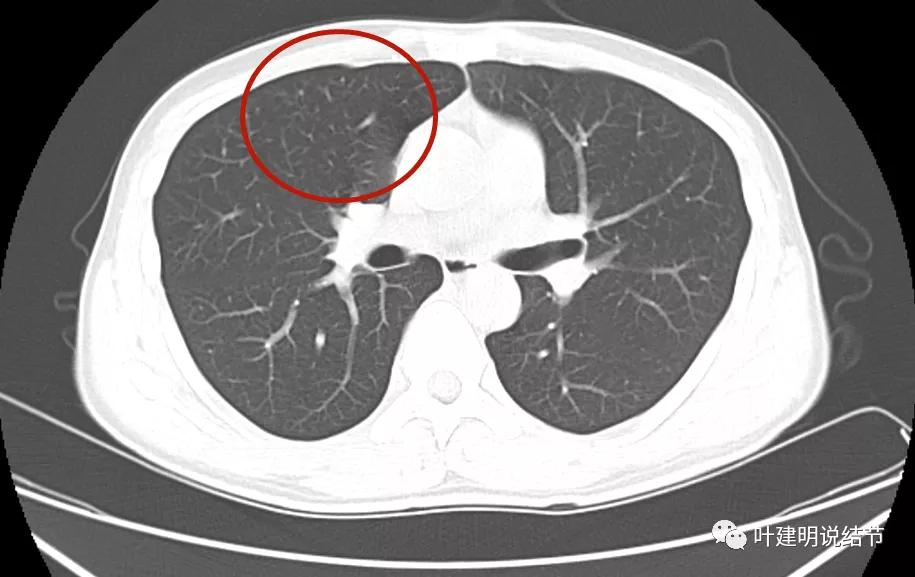

先来看2021年8月的:

病灶1:左上叶结节是混合磨玻璃,但磨玻璃部分密度很低,实性部分密度高,感觉偏散,没有明显收缩力,瘤肺边界模糊不清

病灶2:左下叶极淡的磨玻璃结节,中间似有空泡或偏低密度,但血管似乎有点走向病灶的样子

病灶3:右上叶前段微小淡磨玻璃结节,甚小,2-3毫米许,影像特征不明显,轮廓较清。